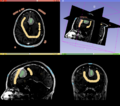

• Topic was generalized to include editor effects based on ITK and VTK

• Marker based watersheds [1]

• Binary watershed to split object [1]

• DoubleThresholding